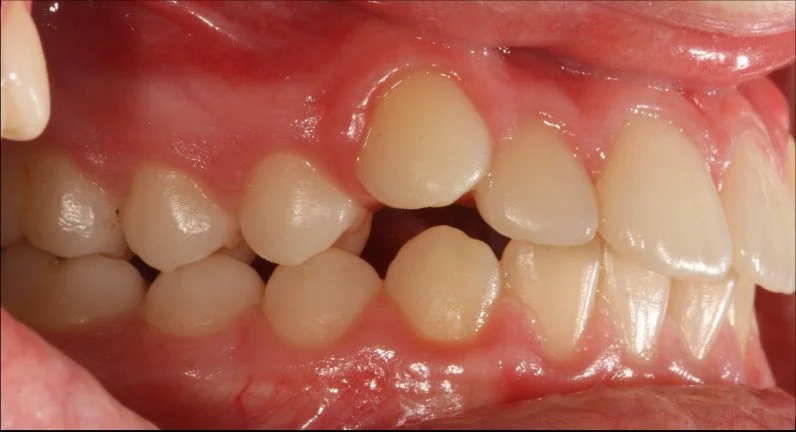

ORTODONZIA INTERCETTIVA + ALLINEAMENTO

BEFORE

Caso di una paziente con morso aperto iniziale e palato stretto, trattato in giovane età con terapia intercettiva mediante espansione rapida del palato. Successivamente, in adolescenza, è stata sottoposta a trattamento ortodontico fisso in dentatura permanente.